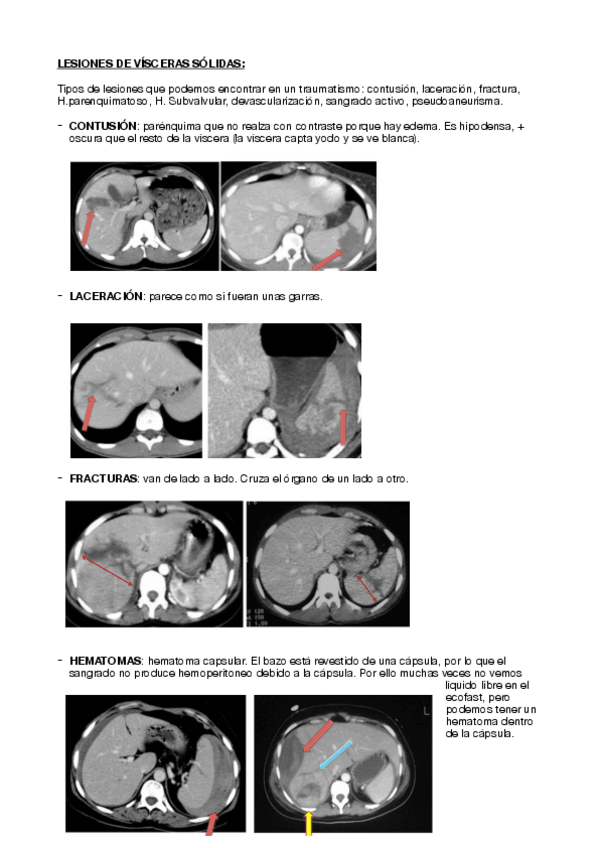

He publicado nuevos apuntes de 4º Diagnóstico Por Imagen: SIMULACRO-DIAGNOSTICO-POR-IMAGEN.pdf

6 páginas